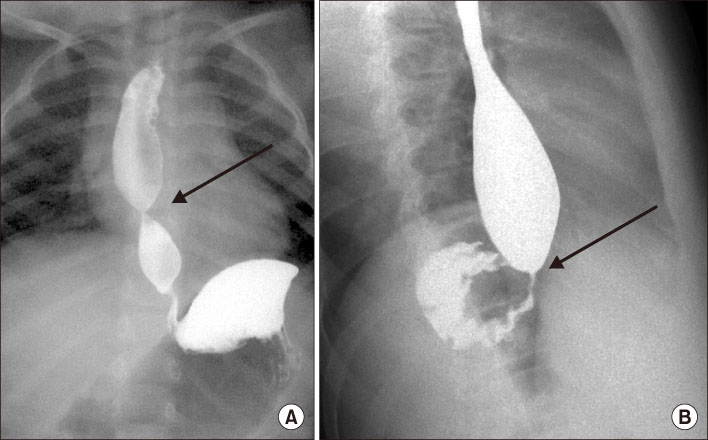

Fig. 2

Upper gastrointestinal contrast study revealed a dilated esophagus proximal to a distal esophageal stenosis (arrows). (A) Anteroposterior view. (B) Lateral view.

Fig. 2 Upper gastrointestinal contrast study revealed a dilated esophagus proximal to a distal esophageal stenosis (arrows). (A) Anteroposterior view. (B) Lateral view.